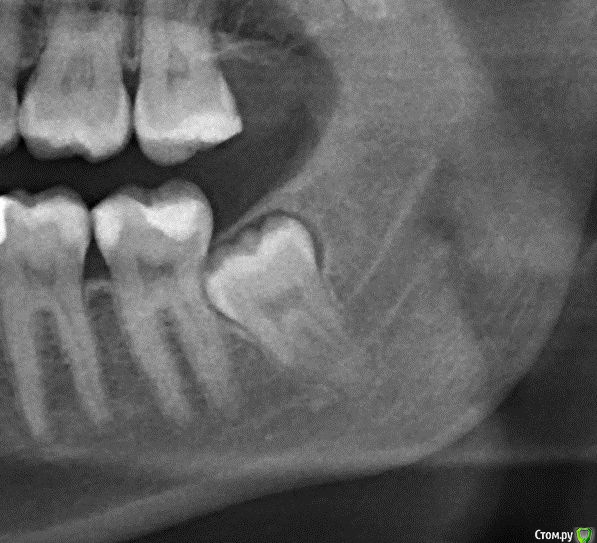

Alena.vsk Опубликовано 30 июля, 2016 Поделиться Опубликовано 30 июля, 2016 (изменено) Здравствуйте, уважаемые специалисты и посетители форума! 4 недели назад был удален 38й зубик. Хирург изначально до операции сделал панораму и 3д томограмму, чтобы понять как проходит нерв, и сообщил, что в моем случае крайне вероятно (99%) возникновение парастезии, до полугода. Т.к. нерв раздавлен зубом, и удалить зуб, не задев нерв, практически невозможно.Удалили относительно быстро: на всё не больше часа, включая уколы и разговоры.Доктор напоследок осмотрел лунку, хотел понять видно ли визуально нерв.В итоге сказал что нерв не виден, остался доволен и уже оценив результат, сообщил что вполне возможно парастезия меня обойдет стороной.Но увы, не обошла: подбородок и нижняя губа онемевшие. Язык и десна - в норме. Заживление в целом проходило и проходит нормально, не считая долго сходившего отека (около 10 дней), но это скорее моя склонность к отекам. Первые дней 10:-очень ломило 31-33 зубы + сильная чувствительность. ПРиходилось пить обезбаливающее.-Подбородок не чувствовал практически ничего. Только при сильном прикосновении чувствовались какие-то оооочень далекие ощущения, даже не похожие на прикосновения. Можно сказать, около 3% чувствительности, и то какой-то не правильной.- нижняя губа первые 10 дней была чуууточку более чувствительна, чем подбородок. Но вместо прикосновений - ощущала только жжение. И даже если губу не трогать - жгло почти постоянно. На сегодня (4 недели после удаления):-Боль 31-33их зубов полностью прошла.-Жжение нижней губы стало намного слабее, но пока слегка сохраняется, и только при мимике и прикосновении. -Подбородок по прежднему "мертвый", подвижек никаких по сравнению с первыми днями. Чувствует только температуру: холодное чувствует хорошо, горячее плохо, только если сочень горячее прикладывать. Изредка чешется, чем доставляет мучения, т.к. "прочесать" зудящее место невозможно. Но кажется (надеюсь не кажется), в кайме губы появилось легкое ощущение чувствительности, похожее на правильное нормальное ощущение. Но только в кайме. В толще губы по прежднему только жжение при прикосновении. с 20ого дня после удаления начала принимать: 1 таб Мильгаммы утром, 1 таб Нейромультивит вечером (по рекомендации хирурга) Собственно ВОПРОС Подбородок и губа- это одна и та же ветка нерва? Можно ли считать, что раз в кайме губы появилась какая-то слабая чувствительность - то значит нерв не перебит совсем и подбородок с толщей губы тоже теперь гарантированно восстановятся?Или же это разные ветки нерва, и если кайма восстановилась, то не факт что восстановится и все остальное? На всякий случай прикладываю рентген и томограмму до, и рентген после. Хирург у меня хороший, пошла к нему по рекомендации от 4х друзей, но очень уж неразговорчивый. На все мои вопросы отвечал "время покажет", давал назначения, промывал лунку и быстренько выпроваживал.Сейчас он на несколько недель в отъезде. И еще один ВОПРОС! По рентгену "после" можно понять, нормально ли затягивается лунка костной тканью? Визуально оценить не могу, т.к. десну зашивали частично, оставлен только разрез между щекой и зубами (разрез по прежднему есть, пока не заживает). Рентген сделан сегодня, т.е. лунке уже месяц. ДО ПОСЛЕ Изменено 30 июля, 2016 пользователем Alena.vsk Ссылка на комментарий